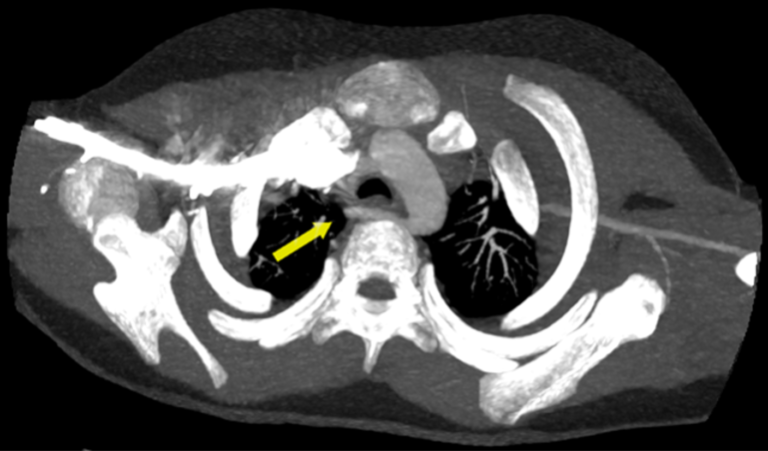

El área de Diagnóstico por imágenes del Hospital Favaloro realizó una angiotomografía de tórax a una paciente pediátrica de tan solo 6 años de edad, donde se visualizó una variante anatómica llamada “arteria subclavia derecha aberrante” con un trayecto retroesofágico generando efecto compresivo del mismo.

Desde el área de Diagnóstico por Imágenes se recibió a una paciente pediátrica, de tan solo 6 años de edad, quien consultó por vómitos de 1 mes de evolución con múltiples consultas en diversos centros de salud y una internación reciente.